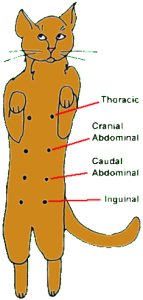

Thoracic – грудная зона;

Cranial abdominal – черепно- брюшная зона;

Cranial abdominal – хвостово-брюшная зона;

Inguinal – паховая зона.У кошек восемь сосков (они имеются как у кошек, так и у котов), которые идут вдоль нижней части тела в двух рядах.

У здоровых представителей этого семейства они бледно-розового цвета и, примерно, 1 см в диаметре. Соски увеличиваются в размерах во время беременности и в период лактации. У котов и небеременных кошек их трудно найти под толстым слоем кошачьей шерсти. Изменения в виде отёка (припухлости) могут возникать у обоих полов, но в основном у кошек, как в одном, так и в нескольких сосках. При этом могут быть затронуты и близлежащие к соску (молочной железе) ткани.

Inguinal – паховая зона.У кошек восемь сосков (они имеются как у кошек, так и у котов), которые идут вдоль нижней части тела в двух рядах.

У здоровых представителей этого семейства они бледно-розового цвета и, примерно, 1 см в диаметре. Соски увеличиваются в размерах во время беременности и в период лактации. У котов и небеременных кошек их трудно найти под толстым слоем кошачьей шерсти. Изменения в виде отёка (припухлости) могут возникать у обоих полов, но в основном у кошек, как в одном, так и в нескольких сосках. При этом могут быть затронуты и близлежащие к соску (молочной железе) ткани.